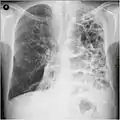

A chest X-ray is not useful to establish a diagnosis of COPD but it is of use in either excluding other conditions or including comorbidities such as pulmonary fibrosis and bronchiectasis. Characteristic signs of COPD on X-ray include hyperinflation (shown by a flattened diaphragm and an increased retrosternal air space) and lung hyperlucency.[5] A saber-sheath trachea may also be shown that is indicative of COPD.[110]

A CT scan is not routinely used except for the exclusion of bronchiectasis.[5] An analysis of arterial blood is used to determine the need for oxygen supplementation and assess for high levels of carbon dioxide in the blood; this is recommended in those with an FEV1 less than 35% predicted, those with a peripheral oxygen saturation less than 92% and those with symptoms of congestive heart failure.[111] WHO recommends that all those diagnosed with COPD be screened for alpha-1 antitrypsin deficiency.[42]